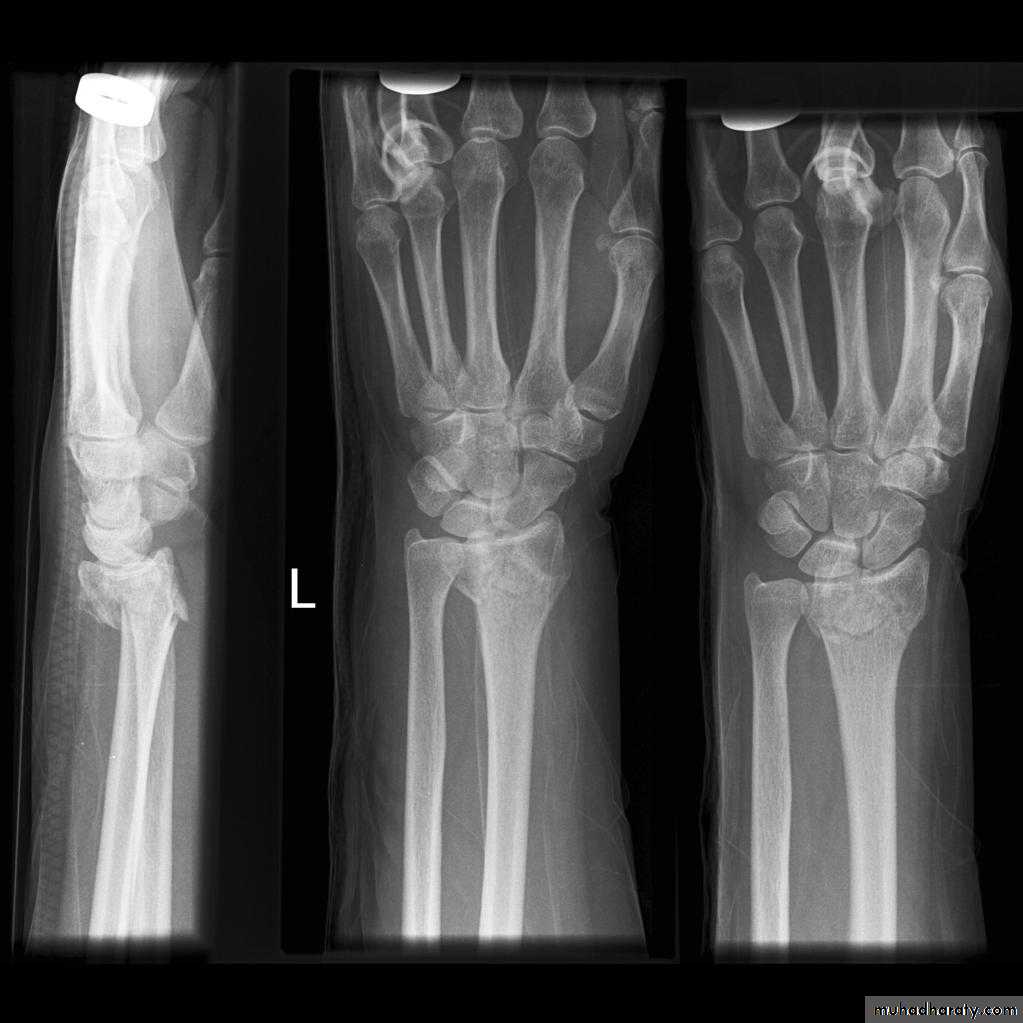

Fall on out stretched hand

xray